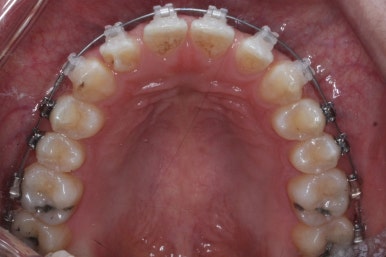

위 사진은 부산치아교정치과에 내원하셨을 대 당시의 입안 모습입니다.

치아들 사이에 전반적으로 틈이 많이 있는 상태입니다.

장치 부착 모습입니다.

이번에 부산치아교정치과에서 사용한 장치는 클리피씨라는 자가결찰 세라믹입니다.

전반적으로 흩어져 있던 틈새를 특정 위치로 모으기 시작합니다.

앞니 사이의 틈을 제일 보기 싫어하실 것 같으므로 앞니 부터 빠르게 틈을 보아줍니다. 대신 작은 어금니 부위로 틈을 모으는 작업을 하게 됩니다.